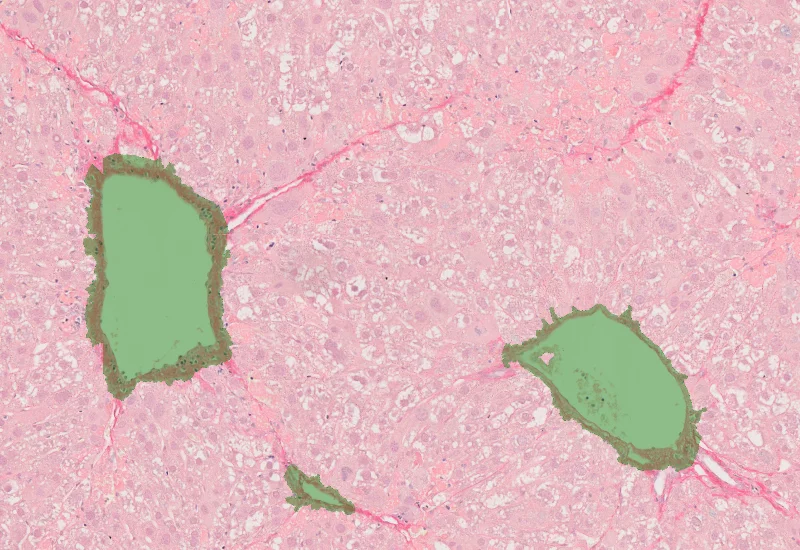

Sirius Red Angio

Detect Sirius Red–stained collagen and blood vessels, and quantify collagen area and total vessel count within the analyzed tissue.

The Angio Sirius Red App detects collagen based on Sirius Red staining as well as blood vessels. As outcome the APP outputs the area of Sirius Red stained collagen as well as the number of detected vessels.

vessel detection